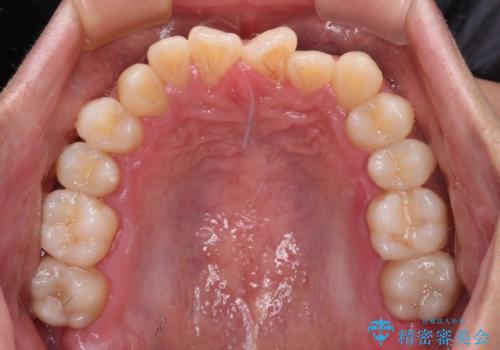

- 前歯のクロスバイトを気にして来院された患者様です。

1年半後に結婚式が控えているとのことで、ワイヤー矯正で早めに治療を終えることを希望されました。

骨格的に下顎が前方に位置していましたが、歯列矯正で改善できると判断し、ワイヤー装置にて矯正治療を行うこととしました。

骨格的な左右差も顕著であったため、正中は合わず、上下前歯の一部が接触しない咬み合わせとなることが予想されましたが、正中はもともとのズレが小さかったことから、合わせることができました。

治療期間も10か月間という短期間で終了し、患者様には大変満足していただきました。